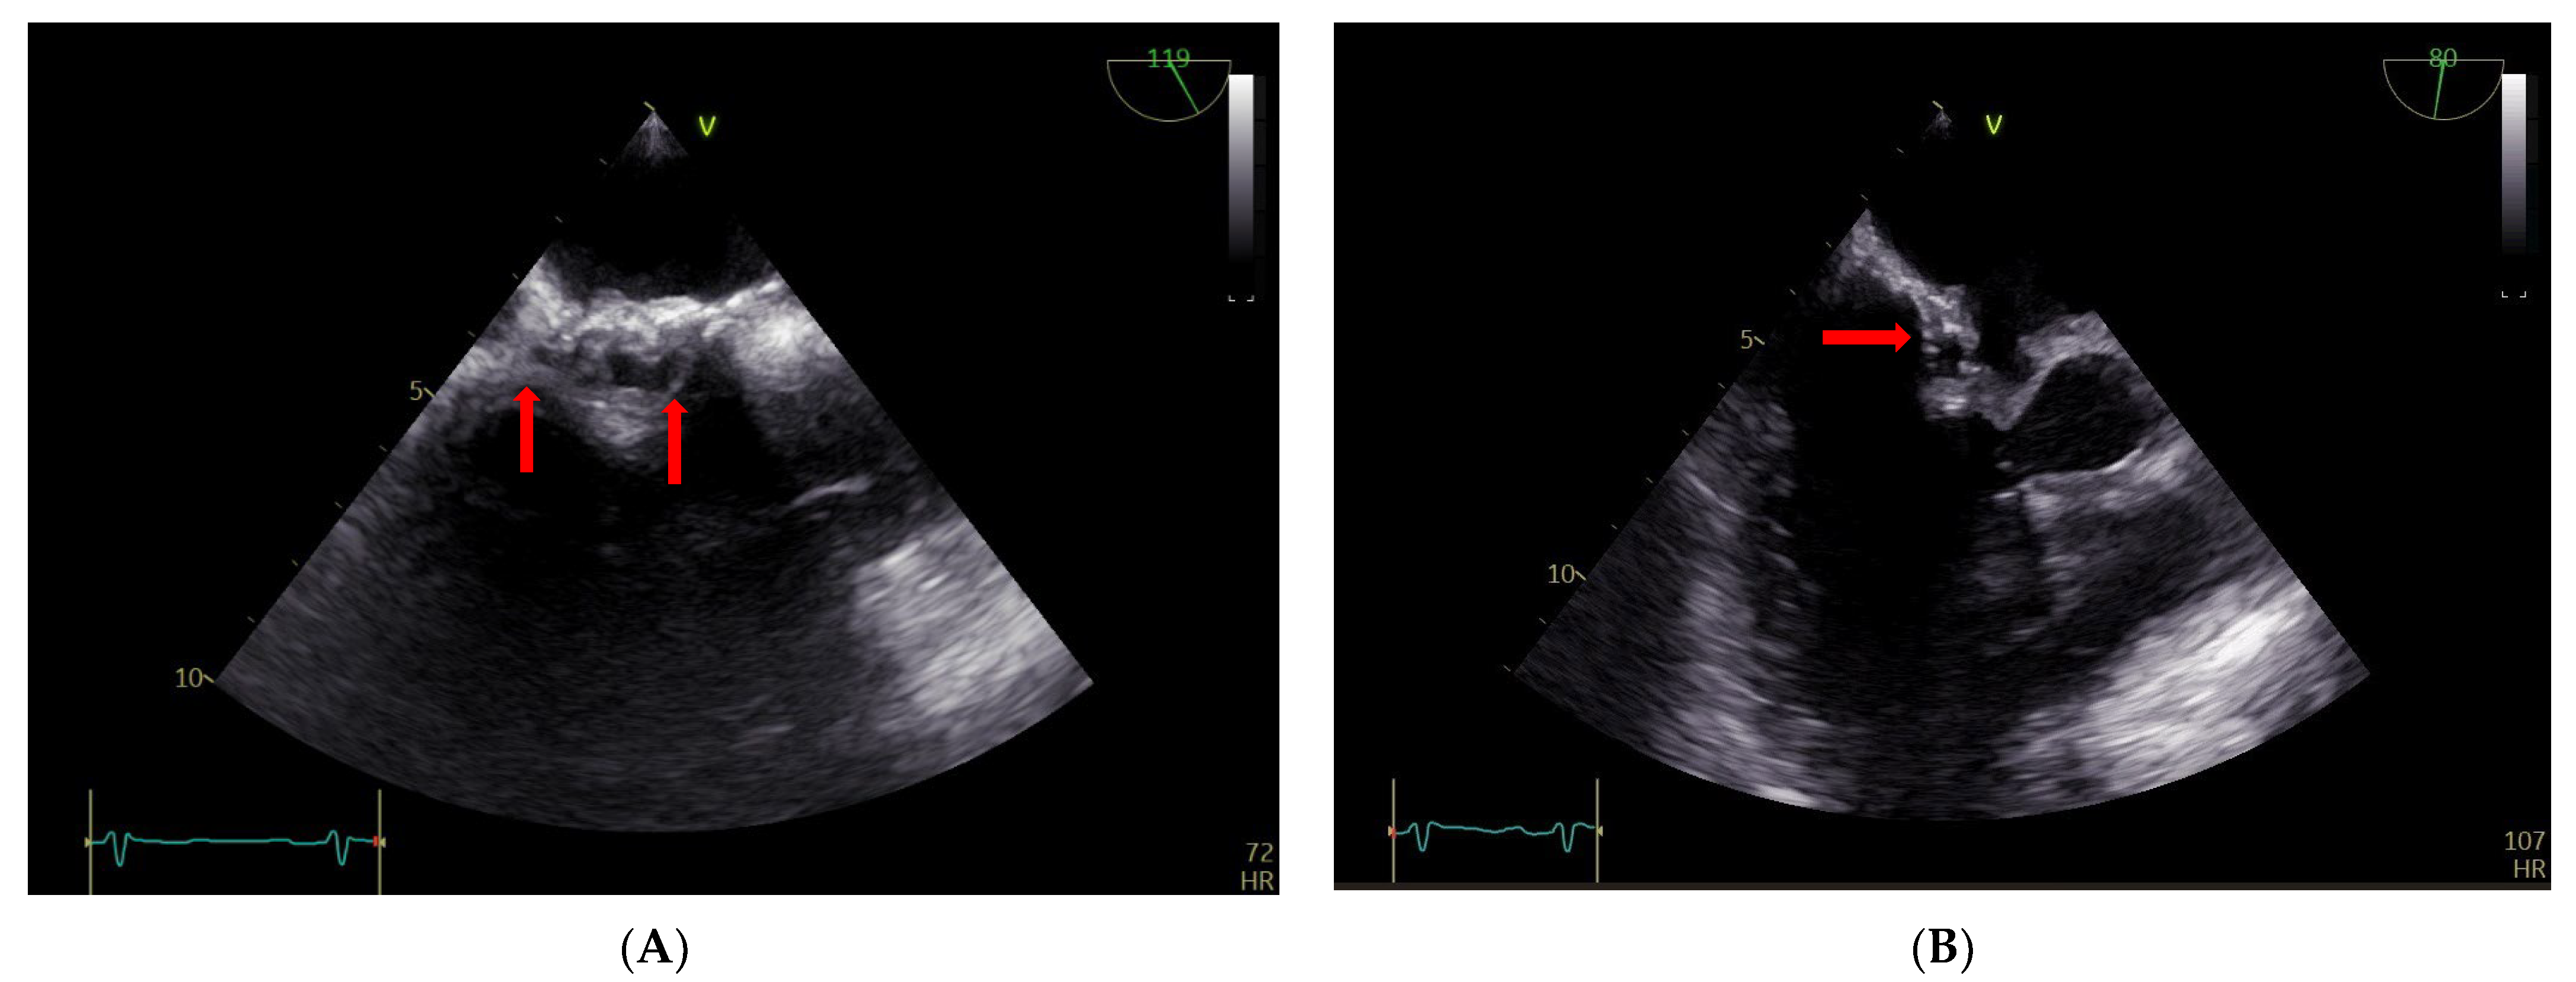

2. Case Report